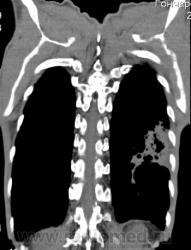

На фоне консолидации полость без содержимого. Может быть всё что угодно, что сопровождается деструкцией. Нужны ещё томограммы в лёгочном окне.

Изображения выставлены все. Ваше мнение уважаемые коллеги?

Туберкулёз.

Туберкулёз?

Это КТ 2-летней давности и попало оно мне в руки, после недавнего прохождения контроля пациентом, когда мы стали перед вопросом о специфическом / не специфическом процессе.

Тогда, пациента 2 месяца лечили от пневмонии, лечили интенсивности, стационарно, в серьёзном учреждении.

Предположу аспергиллез